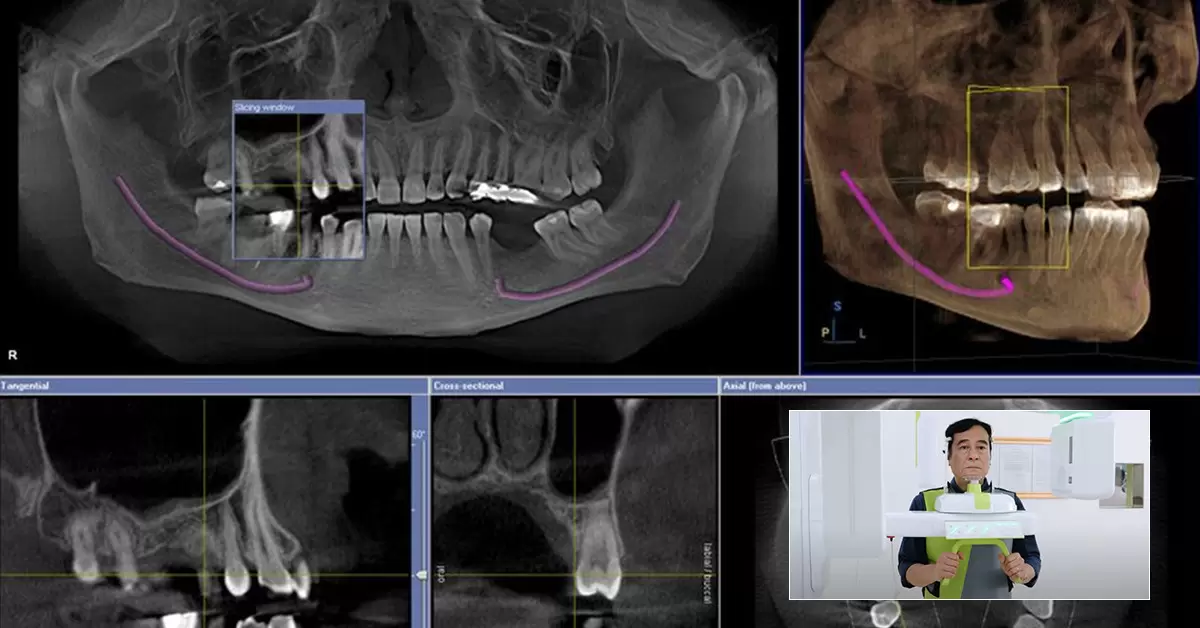

CT Cone Beam (CBCT) là kỹ thuật chụp X-quang hiện đại, sử dụng tia X phân kỳ thành hình nón để tạo ra hình ảnh 3D chi tiết của răng, xương hàm và các mô mềm xung quanh. Đây là phương pháp chụp phim tiên tiến, thường được thực hiện ngay trước khi phẫu thuật hoặc tối đa 3 tháng trước thời điểm phẫu thuật. Cơ chế hoạt động của CT Cone Beam như sau:

• Máy quét quay quanh vùng đầu của cô chú/anh chị, thu thập gần 600 hình ảnh khác nhau từ nhiều góc độ. Trong đó, một vòng quay 200 độ sẽ thu thập dữ liệu thể tích, tạo ra hình ảnh kỹ thuật 3D chi tiết.

• Toàn bộ quá trình thu thập dữ liệu cần thiết chỉ mất vài giây nên không gây phơi nhiễm tia X quá nhiều cho cô chú/anh chị.

• Dữ liệu từ máy sẽ được truyền về màn hình máy tính, giúp bác sĩ phân tích, lên kế hoạch và phác đồ trồng răng chính xác.

Chụp phim cắm Implant CT Cone Beam là kỹ thuật chụp hiện đại, cho phép thấy rõ thể tích và mật độ xương của con người để lập phác đồ điều trị cá nhân hóa

• Đánh giá chính xác tình trạng xương hàm: Máy CT Cone Beam giúp xác định cấu trúc, mật độ và thể tích xương hàm một cách chính xác, từ đó bác sĩ có thể xem xét và quyết định những trường hợp nào cần ghép xương trước khi cấy Implant để đảm bảo quá trình cấy ghép diễn ra an toàn, loại bỏ các nguy cơ đào thải trụ Implant do thiếu xương.

• Xác định chính xác vị trí đặt trụ Implant: Dữ liệu 3D từ máy cho phép bác sĩ phân tích và tính toán vị trí lý tưởng để đặt trụ Implant, đảm bảo độ sâu và hướng cắm phù hợp, tránh va chạm vào ống thần kinh, mô mềm và mạch máu. Việc này giúp giảm thiểu rủi ro và mang lại sự an toàn tối đa cho cô chú/anh chị.

• Nhờ cơ chế quét tia X dạng hình nón (Cone Beam) tạo ra hình ảnh 3D chi tiết của toàn bộ cấu trúc xương hàm, phim CT Cone Beam cung cấp thông tin toàn diện và chính xác hơn so với phim X-quang 2D.

• Khả năng hiển thị lớp cắt từng lát theo chiều ngang và dọc của CT Cone Beam giúp phát hiện các bất thường như rối loạn khớp thái dương hàm, u nang và các tổn thương xương tiềm ẩn mà X-quang 2D không thể phát hiện được do chỉ tạo ra hình ảnh 2D từ một góc cố định.

Sau đó, bác sĩ sẽ hướng dẫn cô chú/anh chị đứng vào vị trí phù hợp nhất trong máy chụp để thu được hình ảnh rõ nét. Máy CT Cone Beam sẽ quay quanh đầu cô chú/anh chị, chụp hàng trăm hình ảnh từ nhiều góc độ khác nhau chỉ trong vài giây.

Những hình ảnh này sẽ được sử dụng để tầm soát cấu trúc xương hàm, mật độ và thể tích xương, giúp bác sĩ lên kế hoạch cấy trụ Implant chính xác nhất, đảm bảo an toàn và hiệu quả trong quá trình điều trị.